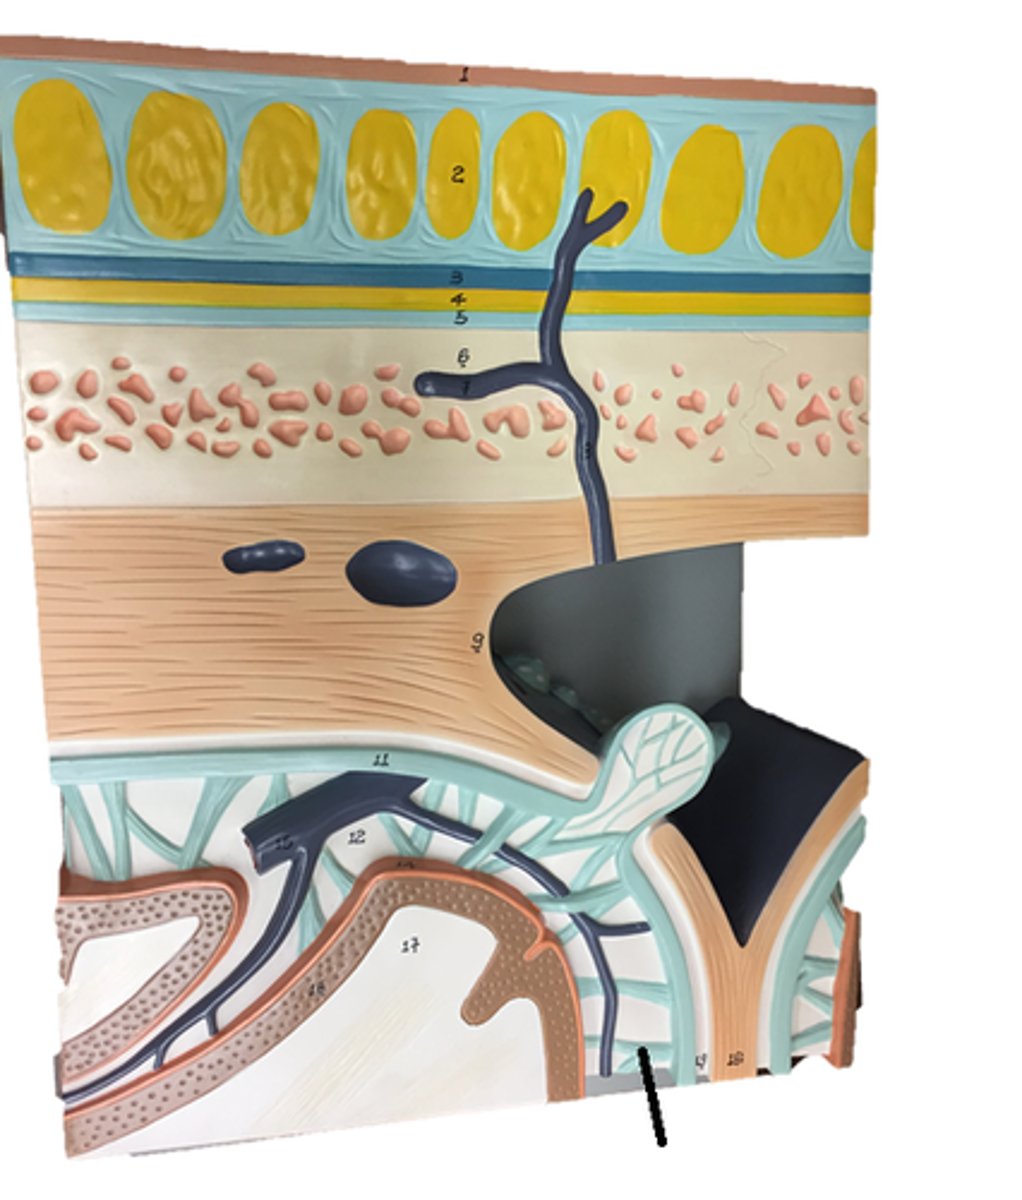

arachnoid villi

arachnoid mater of brain

dura mater of brain

pia mater of brain

falx cerebri

subarachnoid space of brain